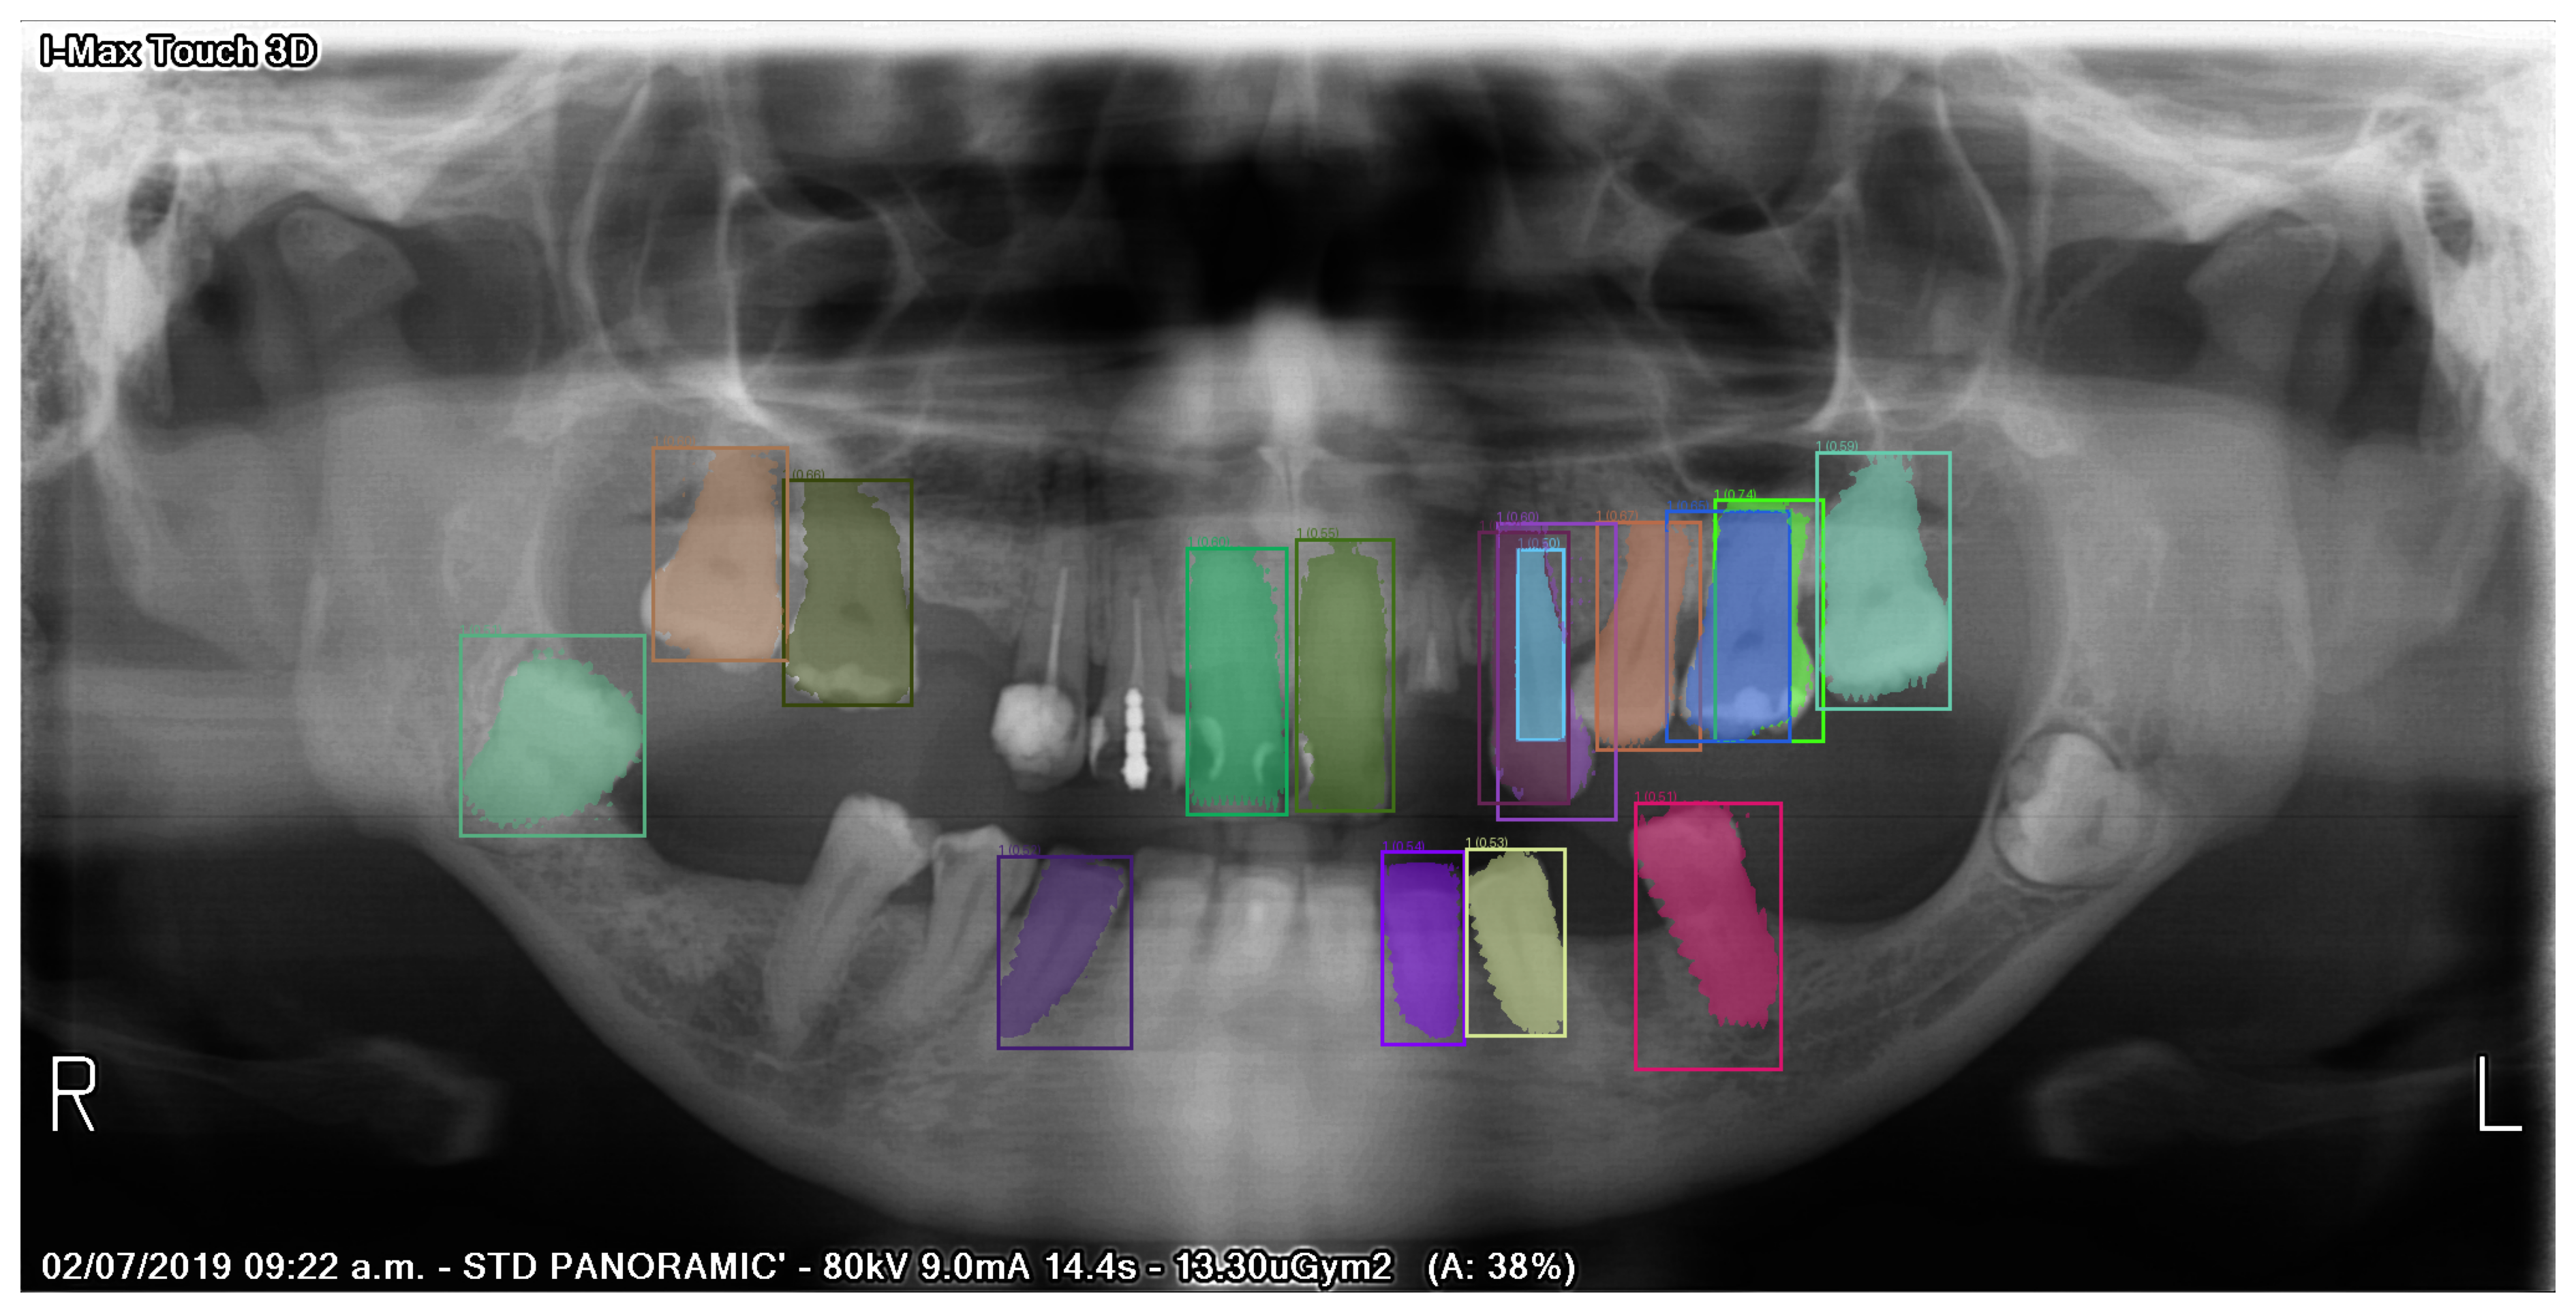

本章では、Kaggle にて CC0 ライセンスのもとで公開されている Teeth Segmentation on dental X-ray images を使用します。このデータセットは、歯のレントゲン画像からなるデータセットであり、歯を領域をポリゴン囲んだアノテーションが含まれています。アノテーションはポリゴンの座標を記載した数値データと画像として保存されたマスクの両方が用意されています。マスク画像は RGB カラー画像で、画像内の色が各歯の番号に対応しています。例えば、13 番目の歯は色が (R, G, B) = (1, 1, 1)、12 番目の歯は (2, 2, 2) のように、32 番目の歯までそれぞれ異なる色で対応付けられています[1]。歯の番号と色の対応関係は、obj_class_to_machine_color.json

ファイルに保存されています。歯の番号を区別して取り扱う際は、この対応表を使用してデータを取得する必要があります。

Fig. 5.3 Teeth Segmentation on dental X-ray images データセットのサンプル画像とマスク画像。#